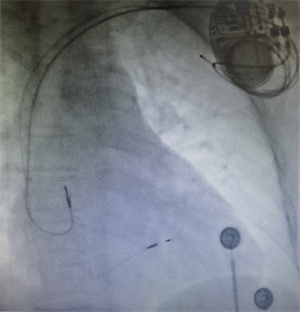

11月17日上午,在邵逸夫医院专家的现场指导下,池州市第二人民医院心内科完成了首例左束支区域起搏术。

左束支区域起搏技术是一种更为生理性的起搏技术,是治疗缓慢性心律失常、纠正心力衰竭的新技术,能够使患者获益最大化、医疗费用最低化,是未来起搏治疗领域的主流方向。首例手术的顺利完成,标志着我院心血管内科紧跟专业主流,在技术层面迈上了新台阶。多年来,心内科一直与医院发展步伐保持一致,持续拓展新技术,致力于为患者提供更优质的医疗服务。